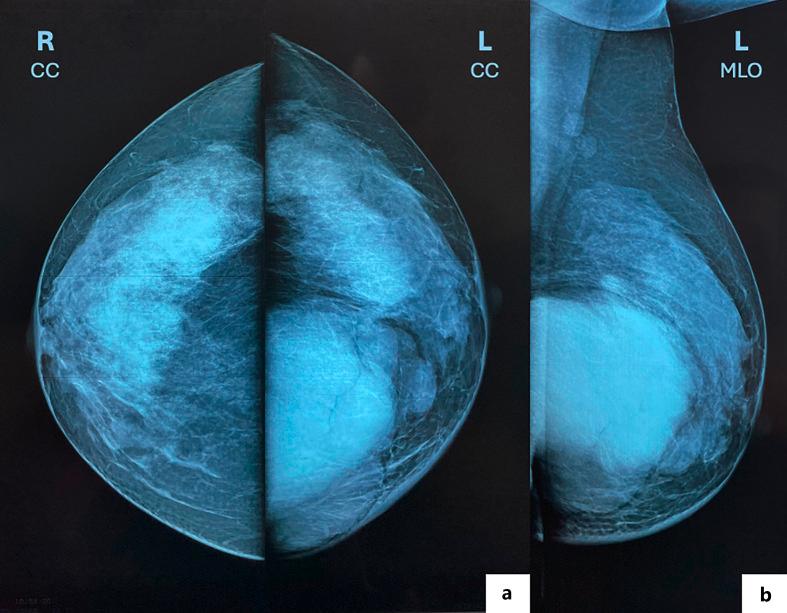

In this report, we describe the case of a 41-year-old woman, who presented with a rapid growth of a phyllodes tumor after an accidental bump on the breast and had to undergo mastectomy followed by breast reconstruction.

在本报告中,我们描述了一名41岁女性的病例,她在乳房意外碰撞后出现叶状肿瘤快速生长,不得不接受乳房切除术,随后进行乳房重建。